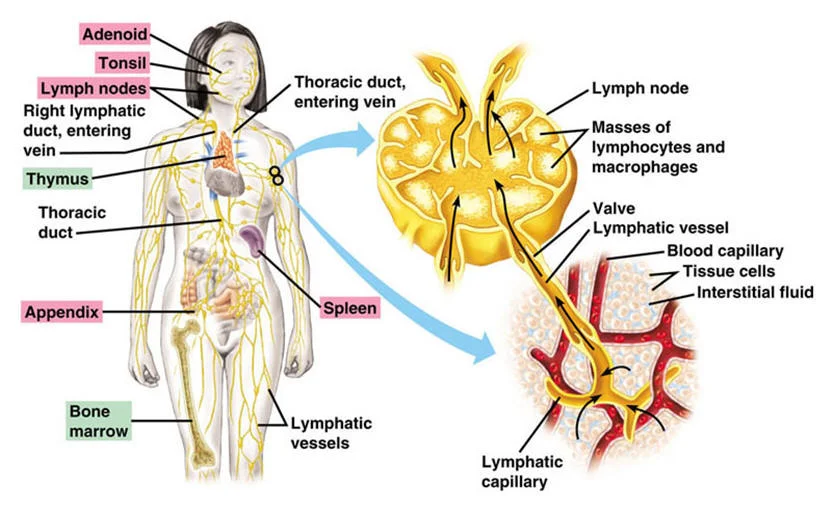

Изображения и схемы: как выглядит лимфа